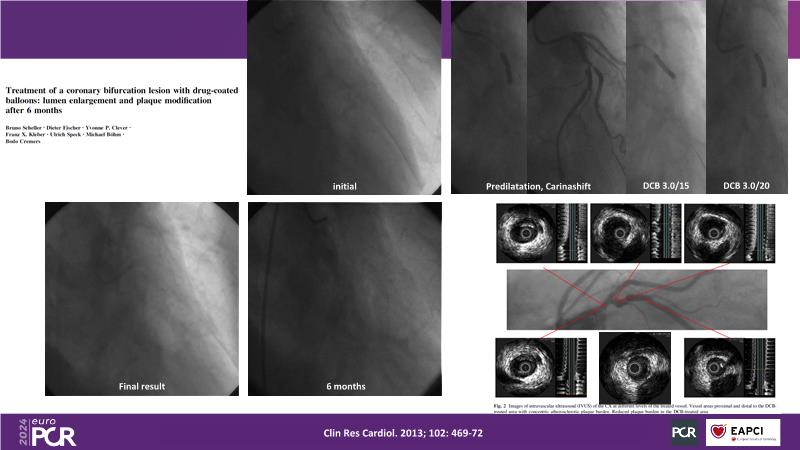

- To learn about practical experiences on DCB in large vessels, bifurcations, multivessel disease and CTO